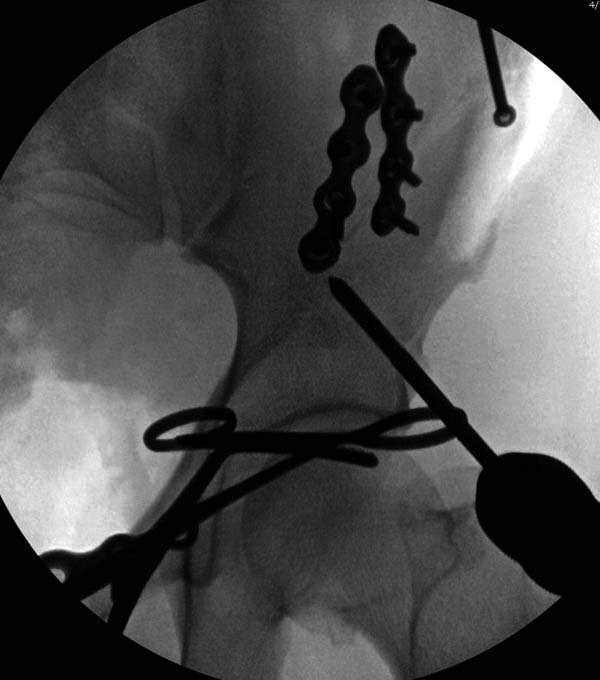

Здесь представлен случай 38 летнего больного (падение с высоты 9 метров) с нарушением тазового кольца. При поступлении для стабилизации передне-нижний аппарат наружной фиксации и на 6й день, вчера, операция из двух доступов.

Представлены снимки техники проведения стержней. Через место прикрепления прямой мышцы в Inferior Iliac Spine в направления вырезки создается жесткость. Weber clamp изнутри таза для репозиции, и фиксация после репозиции перелома крыла подвздошной кости. Наружный аппарат удален, нагрузка предполагается через два месяца.